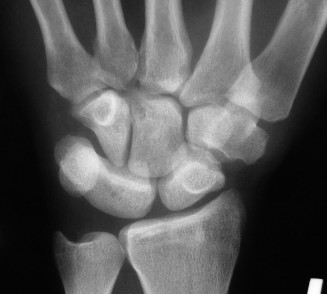

Identify complications of ORIF of hook and hamate fractures? Describe the anatomy of the hamate? CASE 17 A young sportsman presents with the following injury to his thumb ( Figure 3–14** ). What is your diagnosis?**

Figure 3–14(©) Sunil Thirkannad and Christine M. Kleinert.

The correct answer is (E). The lesion shown here is a Bennett’s fracture dislocation.

The correct answer is (D). The abductor pollicis longus (APL) exerts a proximal pull on the distal fragment causing it to migrate proximally while the adductor pollicis causes it to adduct, resulting in the characteristic deformity.